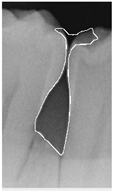

To ensure that only the area framing the symptom is preserved, and to remove the rest of the interfering areas or lines, the symptom frames are extracted according to the closure algorithm, i.e., the maximum connectivity area can be preserved to remove the frames of the non-symptomatic areas, as shown in Figure 7b. After the closure process, some of the frame lines are less smooth than others, which may affect the discrimination accuracy. To deal with this situation, this study performs the filling of the frame lines at the symptom area to facilitate the training of the model. Black and white are chosen to highlight the contrast and to compare the difference in discrimination between the two fill colors, as shown in Figure 7c,d.

Figure 7. Comparison of extracting the closed area and filling. (a) Close operation. (b) Extracting the closed area. (c) Filling with white. (d) Filling with black.